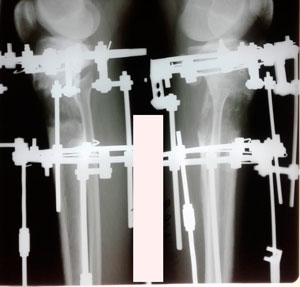

Дата операции - 10.07.2019г.

Дата снятия аппаратов - 01.04.2020

Срок сращения - 9 месяцев.